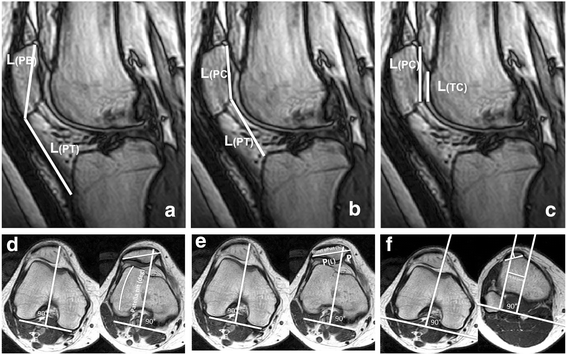

Methods: Twenty subjects (8 males and 12 females) with lateral patellofemoral instability were studied in an open-configuration magnetic resonance imaging scanner in an upright weight-bearing position at full extension (0° flexion) and 15° and 30° flexion with and without the realignment brace. Disease determinants were defined by common patellofemoral indices that included the Insall-Salvati Index, Caton-Deschamps Index, and the Patellotrochlear Index to determine patella height and patella tilt angle, bisect offset, and tuberositas tibiae-trochlear groove (TT-TG) distance to determine patellar rotation and translation with respect to the femur and the alignment of the extensor mechanism.